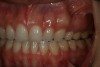

Before bonding, the enamel was etched with 37% phosphoric acid (ETCH-37™ 37% Phosphoric Acid Etchant, BISCO, Inc., www.bisco.com). A dentinal adhesive (ALL-BOND UNIVERSAL®, BISCO, Inc.) was placed, blown thin for 10 seconds with forceful compressed air, and then light-cured for 20 seconds (Figure 4). Using an injectable composite resin (G-ænial Universal Flo), a sequence of composite resin layering was performed to blend the composite resin to the existing tooth and create a natural polychromatic effect. To match the chromaticity along the gingival area, an opacious dentin shade, AO2, was bonded over the RMGI to mimic the lost dentin (Figure 5). Using a free-hand sculpt technique, universal shade A2 was injected over the opacious dentin composite resin with an emphasis on placing a convex anatomy to simulate natural dentition. Because of the chameleon effect and the depth of color of the body shade A2, no other shades were needed (Figure 6).

After final light-curing, esthetic contours were refined using aluminum oxide finishing discs (Sof-Lex™ Finishing Disc, 3M ESPE, www.3mespe.com) and Q-Finisher® composite resin finishing burs (H50AQ, Komet USA). Finally, microdiamond-infused polishing wheels and 1.0-µm microdiamond polishing paste brought out the surface luster of this injectable composite resin (Figure 7 and Figure 8). Using proper technique and state-of-the-art dental materials, natural color, contour, and finish to mimic tooth were achieved.12